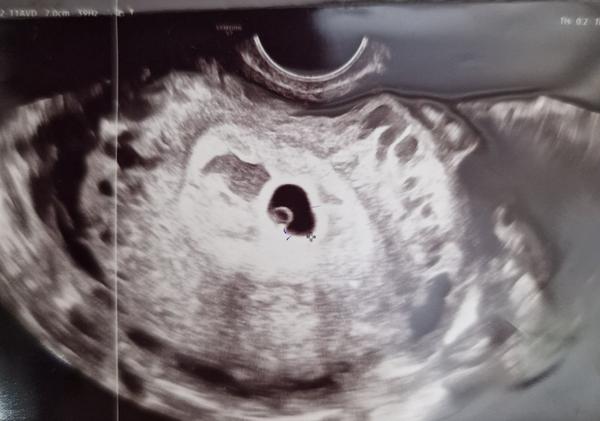

5+5, ešte ale nebolo vidieť plod.